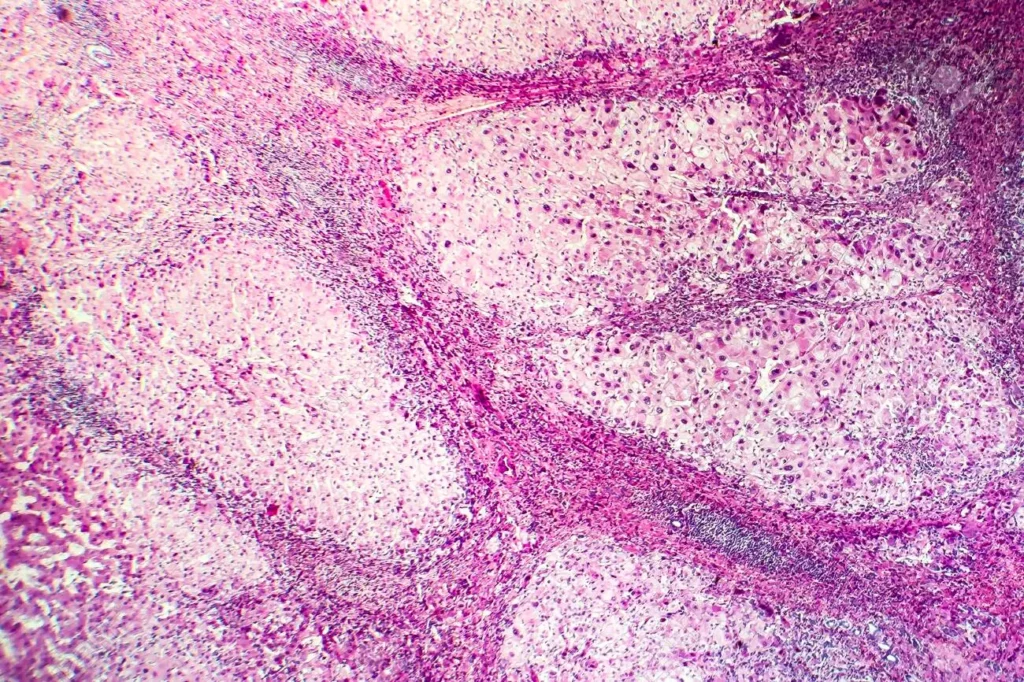

La cirrosis se caracteriza por la formación excesiva de tejido cicatricial (fibrosis) en el hígado. Esta fibrosis reemplaza gradualmente el tejido hepático normal y conduce a una alteración de la arquitectura celular normal del hígado. Las células hepáticas pierden su disposición regular en placas o láminas y se encuentran dispersas en pequeños grupos dentro del tejido cicatricial.

A medida que progresa la cirrosis, pueden formarse nódulos de regeneración en el tejido hepático. Estos nódulos son áreas pequeñas de tejido hepático regenerado que se desarrollan como una respuesta a la lesión crónica y la muerte celular. Los nódulos de regeneración son característicos de la cirrosis y contribuyen a la distorsión estructural del hígado.